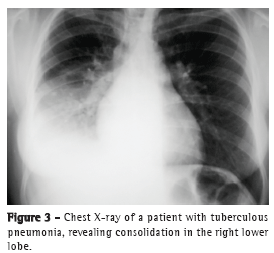

The most common radiological findings are reticular infiltrates and consolidation,(5,6,10,15,17) and cavitation can occur in 27-50% of cases.(6,10,16) Figures 1 to 4 show some of the main radiological patterns in this context.

The leading cause of ICU admission was respiratory failure, and Acute Physiology and Chronic Health Evaluation II (APACHE II) scores ranged from 13 to 23 in most of the studies.(5,6,10,15,17) Some authors evaluated the factors associated with the development of respiratory failure and the need for MV. Gram-negative pneumonia or sepsis, COPD, history of poor compliance with tuberculosis treatment, and cancer were predictors of respiratory failure.(9) In a series of 13 cases, 7 and 6 patients, respectively, had miliary/disseminated tuberculosis and tuberculous pneumonia requiring intensive care. Patients with miliary/disseminated tuberculosis were more likely to require MV than were those with tuberculous pneumonia (18.9% vs. 0.8%; p < 0.0001).(8)

The time from onset of symptoms to initiation of antituberculosis treatment has been reported to be over 30 days in 28.8-34.0% of cases.(6,17) The time from admission to initiation of appropriate treatment was evaluated in only one study, which reported a mean of 4.3 days. In that retrospective study, the time from admission to initiation of treatment was shorter in patients with miliary tuberculosis than in those with tuberculous pneumonia (2.8 ± 2.5 days vs. 5.0 ± 7.0 days; p = 0.048).(16) There can be a delay in diagnosis and, consequently, in initiation of treatment because it is difficult to differentiate tuberculous pneumonia from severe bacterial pneumonia on X-rays. Considering this difficulty in distinguishing the two pathologies, one study evaluated the differences between ICU patients with severe pneumonia and tuberculosis and those with severe pneumonia without tuberculosis in terms of their clinical and radiological characteristics. Symptom duration longer than two weeks and the presence of micronodules or a cavitary pattern on chest X-ray were significantly associated with active pulmonary tuberculosis.(20) In addition, a miliary pattern on chest X-ray can also be misinterpreted as congestive heart failure.(18)